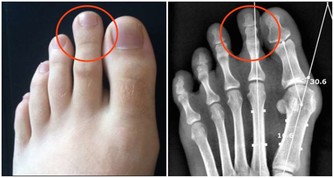

這也就罷了,關鍵是,孩子正餐還要吃很多肉。在臨床中,經常有幾歲的小女孩,過早乳房發育,甚至形成結節,均與飲食中過多肉蛋奶有很大關係,營養過剩,促使孩子過早發育,過早成熟。

對於成年人來說,大魚大肉,營養過剩,從而引起各種慢性疾病,被稱為“富貴病”,這就不用我贅述了吧?